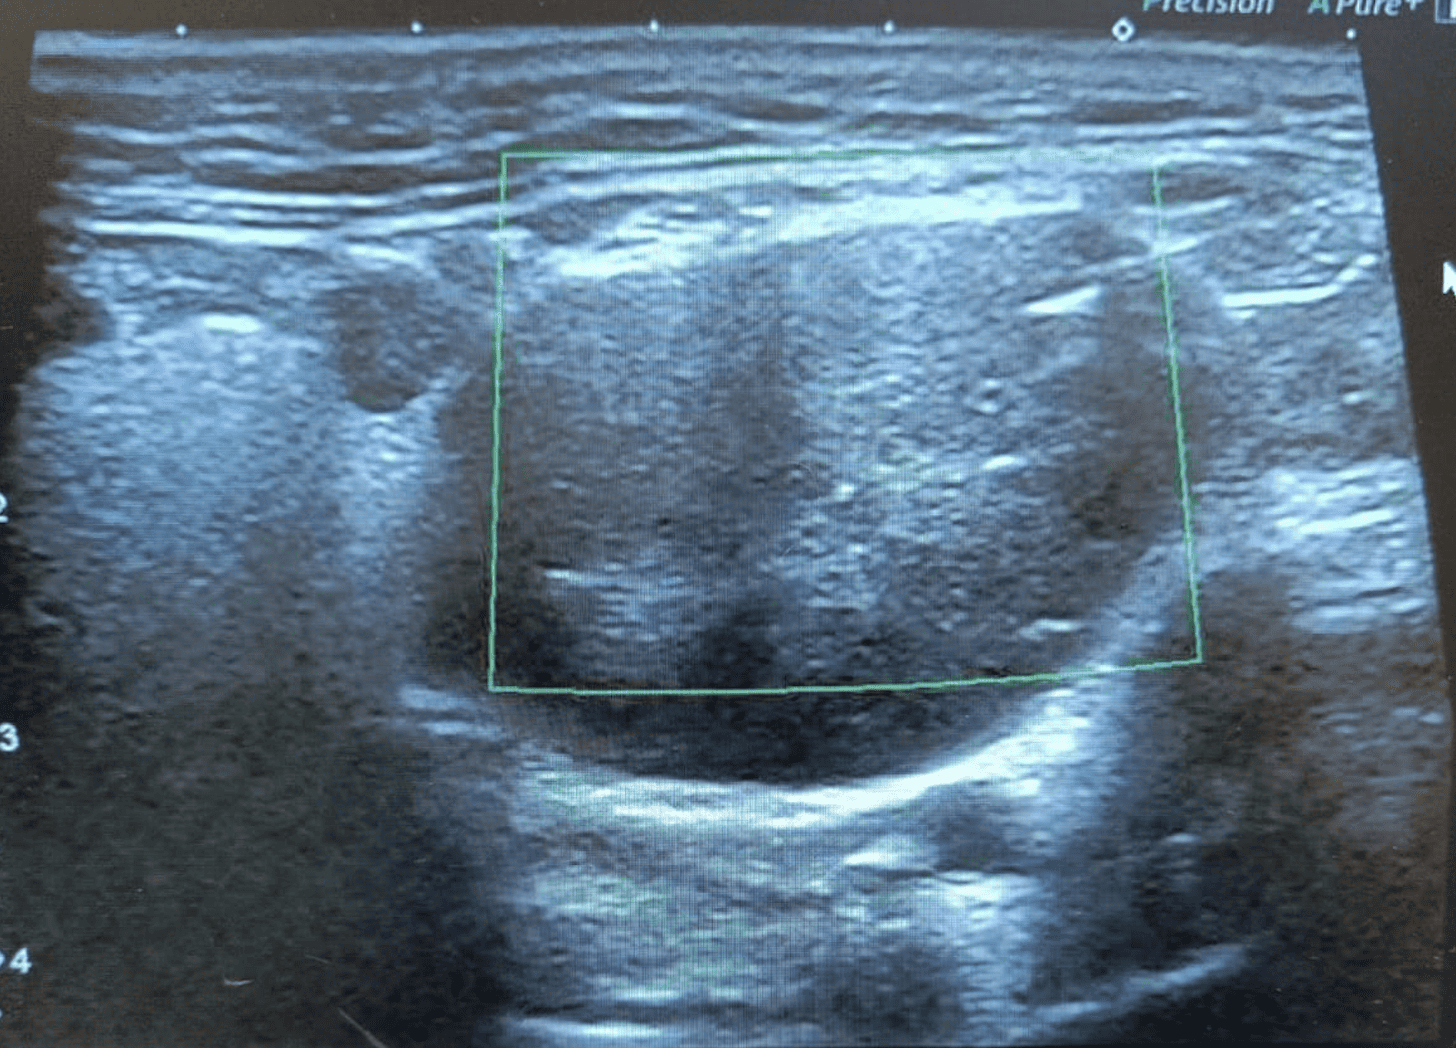

Hallazgos ecográficos

Ecografía cervical que muestra adenopatías hipoecoicas sólidas. En lado izquierdo, imagen de 24x32 mm con vascularización periférica en Doppler; en lado derecho, adenopatía de 20x18 mm con características similares. Hallazgos sugestivos de posible etiología maligna.